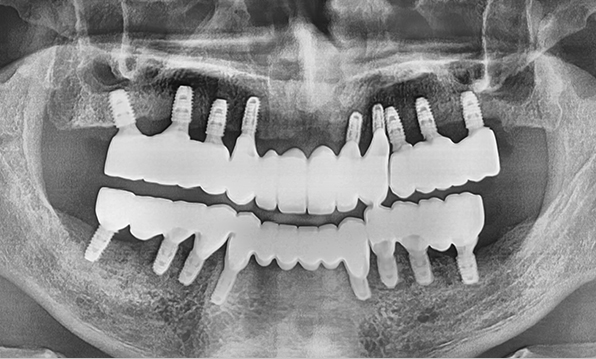

3D 디지털 진단을 통한 체계적인 계획

전체 임플란트는 위턱과 아래턱의 교합, 잇몸뼈의 상태 및

얼굴 변화 등 모든 것을 고려해 식립해야 합니다.

서울더자연치과는 3D 디지털 기술의 정밀 진단을 바탕으로

수술 계획을 세워 수술을 집도합니다.

치료기간 : 2021.04.12~2021.09.15